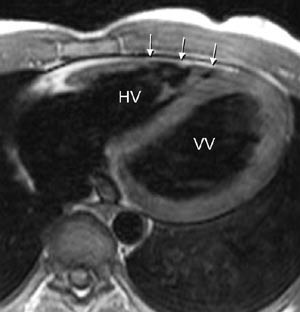

Ikke-invasiv bildediagnostisk utredning av medfødt hjertesykdom er i første rekke en oppgave for ekkokardiografi med doppler. Bruken av MR er derfor langt på vei bestemt av hvor langt man kommer med den undersøkelsen. MR er særlig godt egnet til å avklare komplisert anatomi (3, 4) og kan også bedre enn ekkokardiografi brukes til å vurdere både høyre og venstre ventrikkels funksjon (7). MR kan benyttes ved postoperativ kontroll av flere tilstander (3, 5), ikke minst hos barn og unge. Ved en forholdsvis enkel tilstand som coarctatio aortae (fig 1) vil MR alene som regel gi tilstrekkelig informasjon både pre- og postoperativt (3).